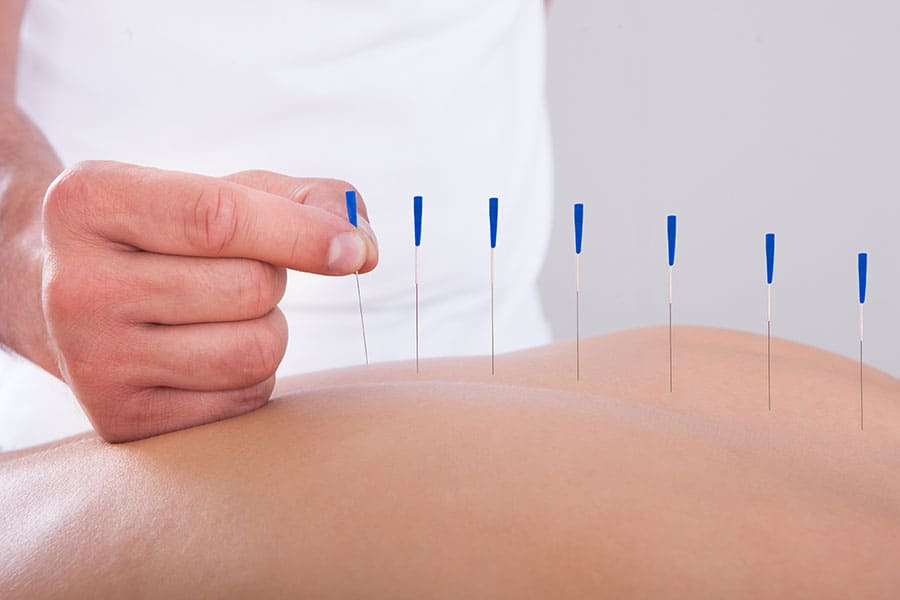

Advanced Practice Providers, Clinical Nurse Specialists, Nurse Practitioners, Nursing, Physician AssistantsClinical Uses of Acupuncture

Complementary alternative medicine (CAM) and treatments have received much attention and acclaim in the past years. Many patients…